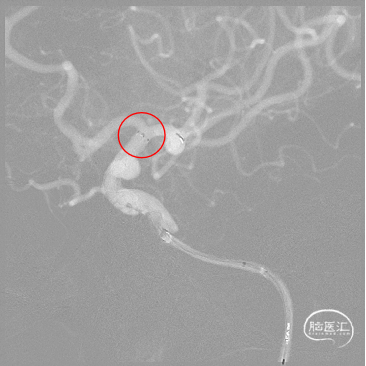

术前DSA造影:

左侧颈内动脉眼动脉段动脉瘤。

左侧颈内动脉眼动脉段动脉瘤:动脉瘤约为6.21*5.11mm(H*W),瘤颈宽约为4.72mm。

载瘤动脉近端锚定点直径:4.72mm

载瘤动脉远端锚定点直径:3.54mm